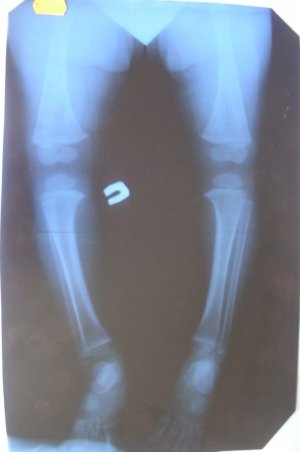

Доброго времени суток! У ребенка искривлены голени ног, при ходьбе заметно, и правая нога косолапит. Хирург из поликлиники поставил диагноз Варус голеней, сказал делать массажики, возможно выпрямятся ножки. Обратились к ортопеду, он нас отправил на ренген, В больнице где делали рентген, в карточке по этому снимку сделали запись "аномалий развития изменений деструктивного характера не выявлено", ортопед в свою очередь поставил диагноз Болезнь Блаунта. Назначил корректоры на обе голени. Хотелось бы знать, какой диагноз верный. когда ребенок начинал ходить ножки были О-образные, сейчас более менее выровнялись, а голени деформированы. Снимок рентена прилагаю. Подскажите пожалуйста, что делать в нашей ситуации...